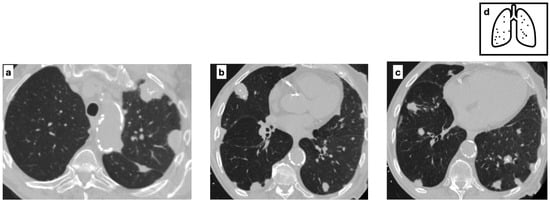

Figure 6.

CT scans of a Patient with a diagnosis of sarcoidosis demonstrating multifocal nodules characterized by central calcifications (a–c) and calcified lymph nodes are present within the mediastinum (d). Mediastinal lymphadenopathy in sarcoidosis is typically bilateral and symmetric; lymph nodes may calcify over time, commonly exhibiting ‘popcorn’, amorphous and punctate calcifications. Pattern of calcification (e).